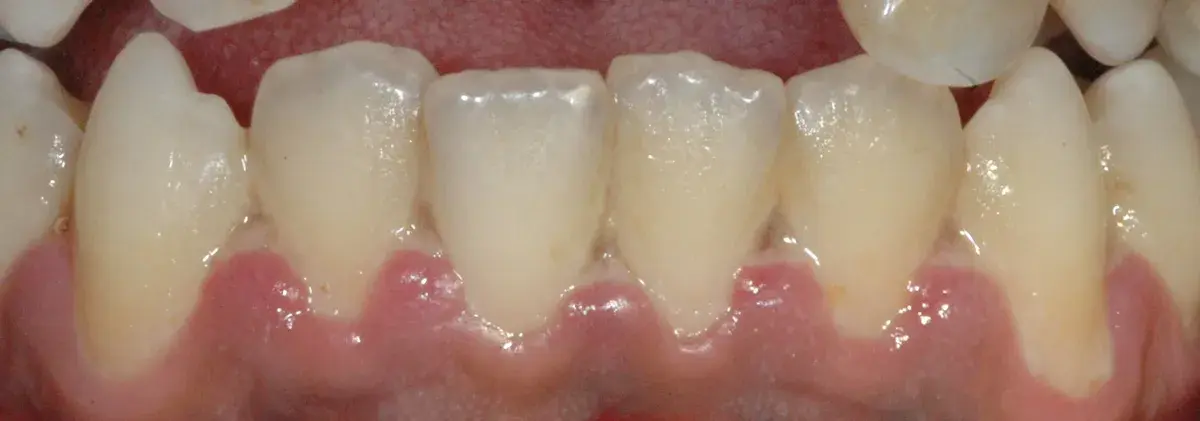

Perché le gengive si ritirano, quando preoccuparsi e cosa può fare il parodontologo. Classificazione di Cairo, innesto connettivale, lembo coronale.

Le recessioni gengivali possono essere corrette o meno. Esistono indicazioni assolute e relative al trattamento chirurgico con copertura radicolare.